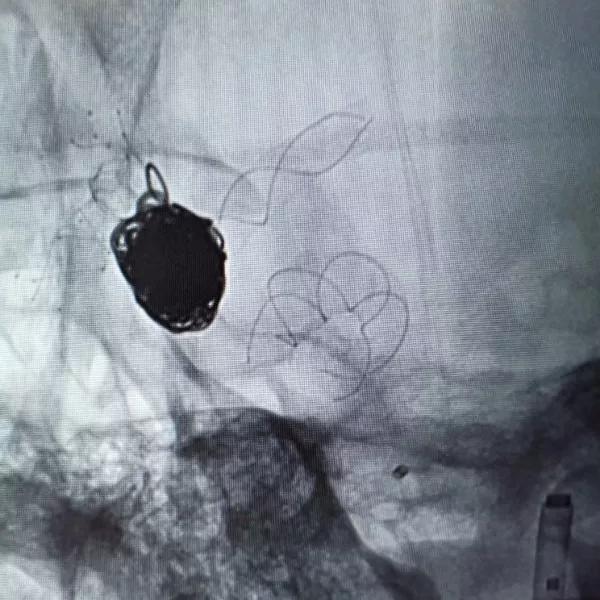

然后再次通过支架并达到右侧大脑中动脉,向海绵窦段多发动脉瘤输送并释放4.0×30mm Tubridge®支架。

▲各角度观察显示Tubridge®贴壁良好

▲造影见造影剂滞留,载瘤动脉通畅。